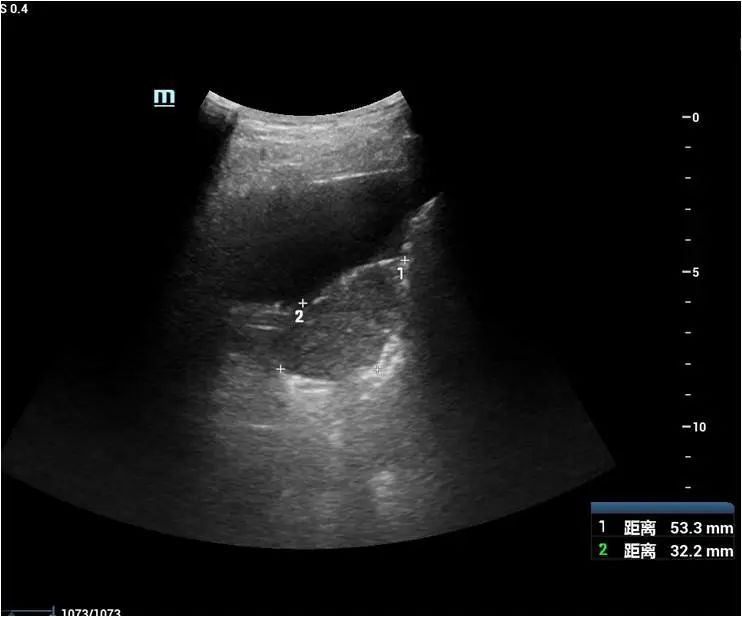

超声医学科接诊该患者后先行超声检查+超声造影评估,于右侧背部肋间检查发现患者右肺下叶低回声肿块,大小约53×32mm,可见斑片状强回声及无回声,CDFI:见血流信号。超声造影见该团块早于周围组织灌注,灌注不均匀,灌注峰值高于周围组织,内见少许无灌注区。